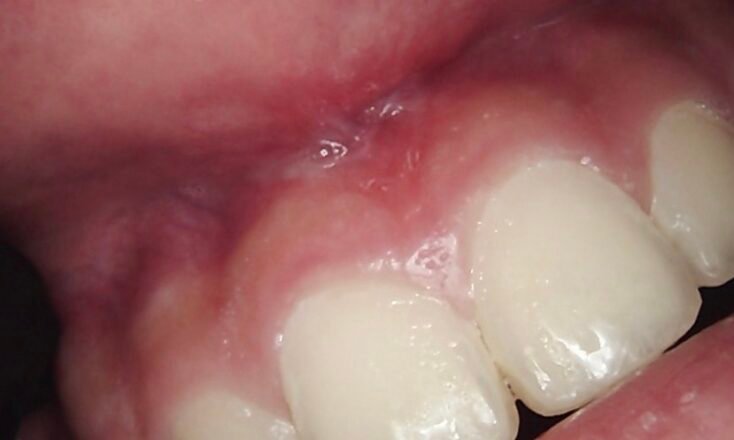

Relieving Restricted Mobility (Lip-Tie): When a tight frenum restricts lip movement or causes gaps between front teeth.

Laser Frenectomy (Lip-Tie & Tongue-Tie): A quick, gentle procedure to release tight muscle attachments, improving speech and preventing future gum recession.